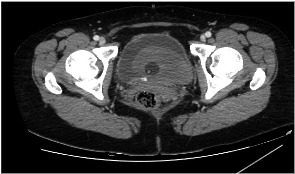

Patient was admitted to interventional radiology departament for embolization of the bleeding vessel int resected part, before it drainage and lavage of urinary bladde was perfomed and hemotransfusion started.

Right femoral artery was punctuated under local anesthetic. Inferior segmental artery was selectively catheterized and pseudoaneurysm was visualized. A microcatheter was inserted into segmental branch (Figure 4).